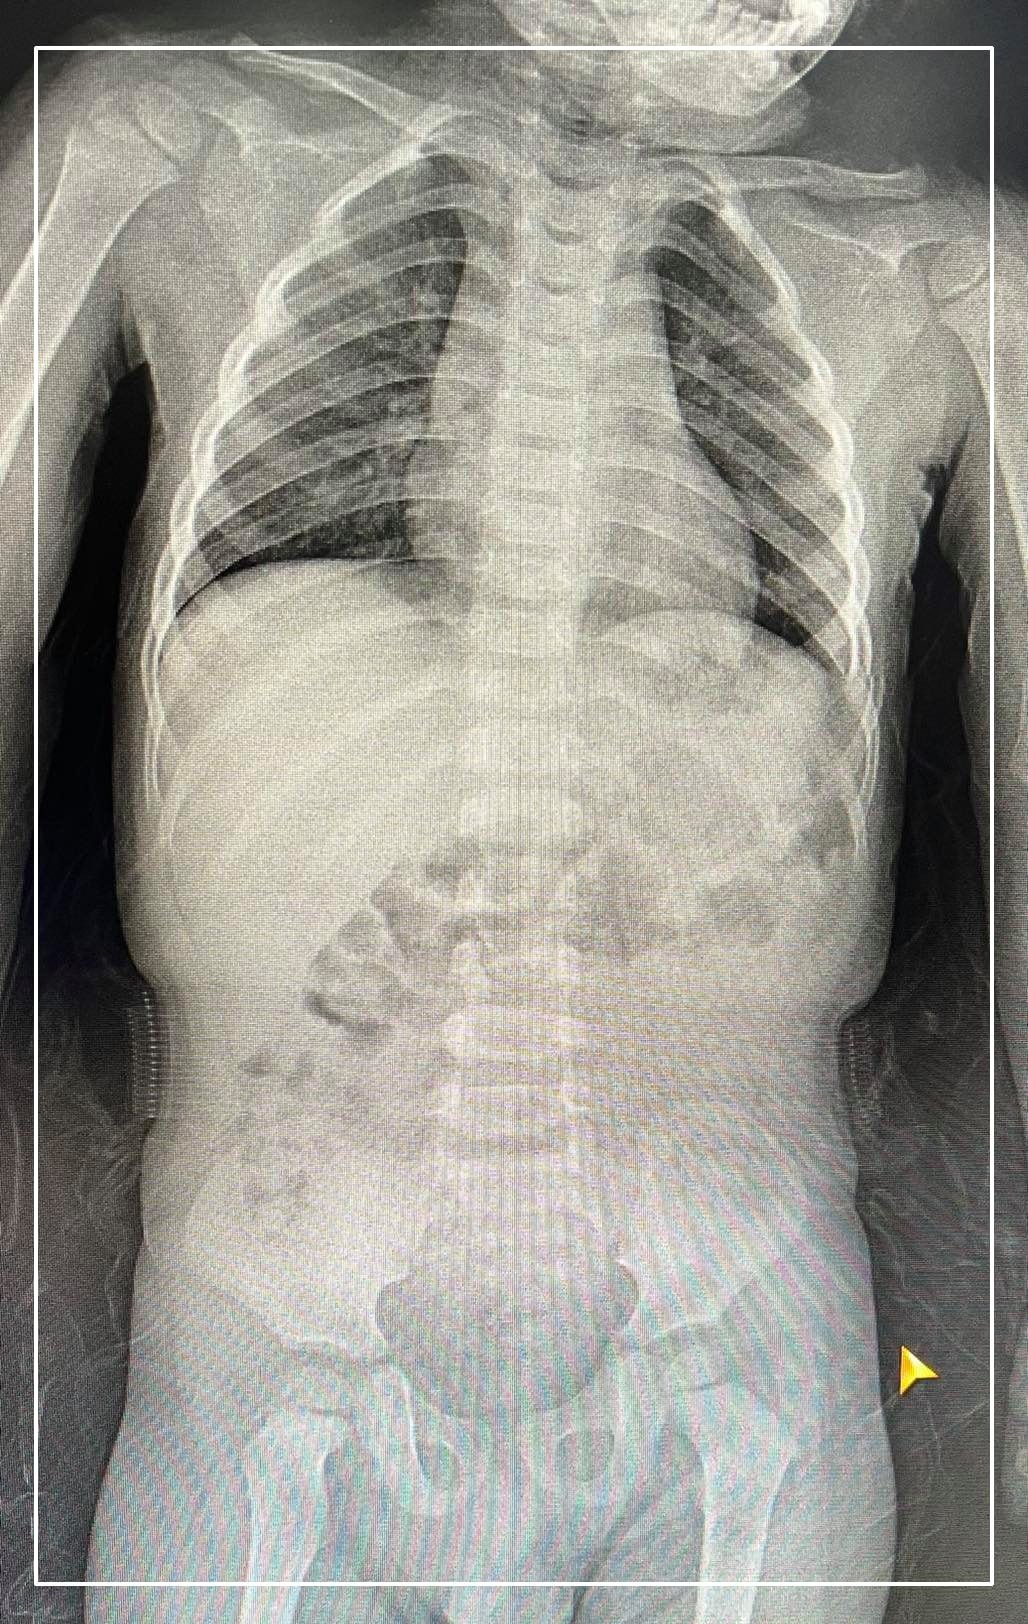

ГССҮТ сүүлийн дижитал рентген аппаратаар бүтэн биеийн рентген зураг авах боломжтой боллоо

Гэмтэл согог судлалын үндэсний төвийн Дүрс оношилгооны тасаг нь Хүлээн авах яаралтай тусламжийн хэсэгтээ Эрүүл мэндийн яамны санхүүжилтээр Япон улсад үйлдвэрлэсэн хитачи брендийн 2021 онд үйлдвэрлэгдсэн Раднекс-50 загварын бүтэн дижитал рентген аппарат суурилуулсан байна.

Тусгай программын тусламжтайгаар бүтэн биеийн рентген зургийг авах боломжтой болсон юм.